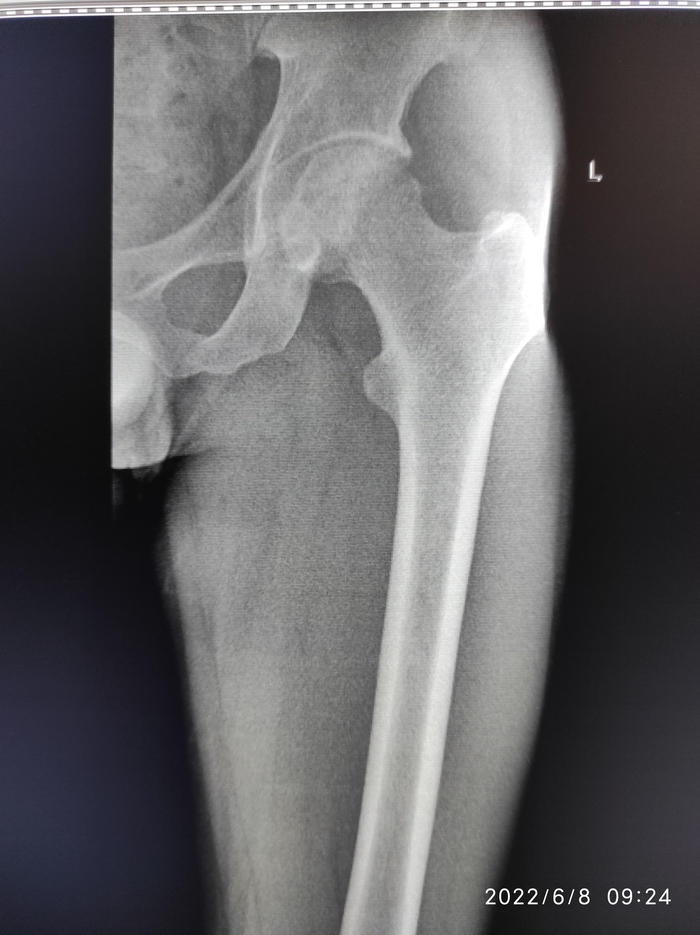

Сказали нужна операция

В общем сказали нужно менять головку бедренновой кости на железную. Пока пытаюсь записаться на консультацию в республиканскую больницу. Я пока ещё не совсем понимаю что за операция и долго ли проходит реабилитация. Кто сталкивался с таким прошу рассказать. У меня боли начались года 2 назад. Могу ответить в комментариях, если интересно.